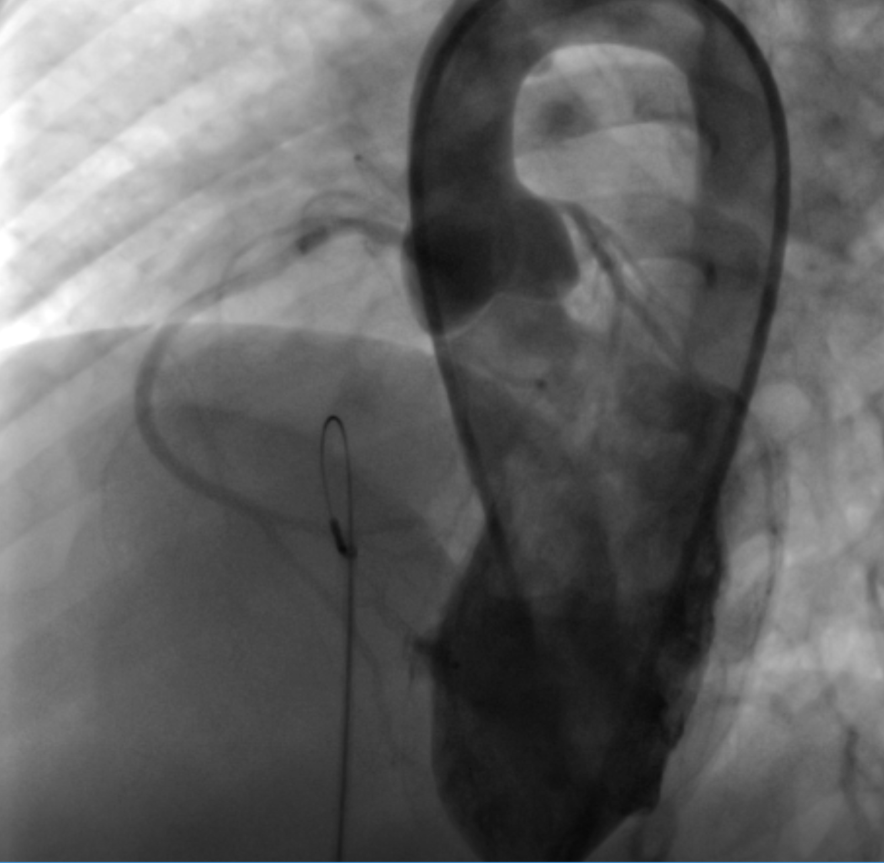

经过多学科的讨论会诊,并在儿童血液科李原主任和儿童心内科吴蓉洲主任的通力合作下,决定挑战“出凝血障碍”这一手术禁区。小霖经过多次输注新鲜冰冻血浆,非常顺利地完成了室间隔缺损的介入封堵治疗,术后无任何并发症,顺利出院。

吴蓉洲主任介绍,自我科开展先天性心脏病介入近20年来,室间隔缺损的介入封堵已经达到了1800余例,然而同时存在严重凝血功能障碍的患者尚属首例。有了本例的成功经验,相信会有更多类似的患者会得到更好的治疗!

封堵前

封堵后